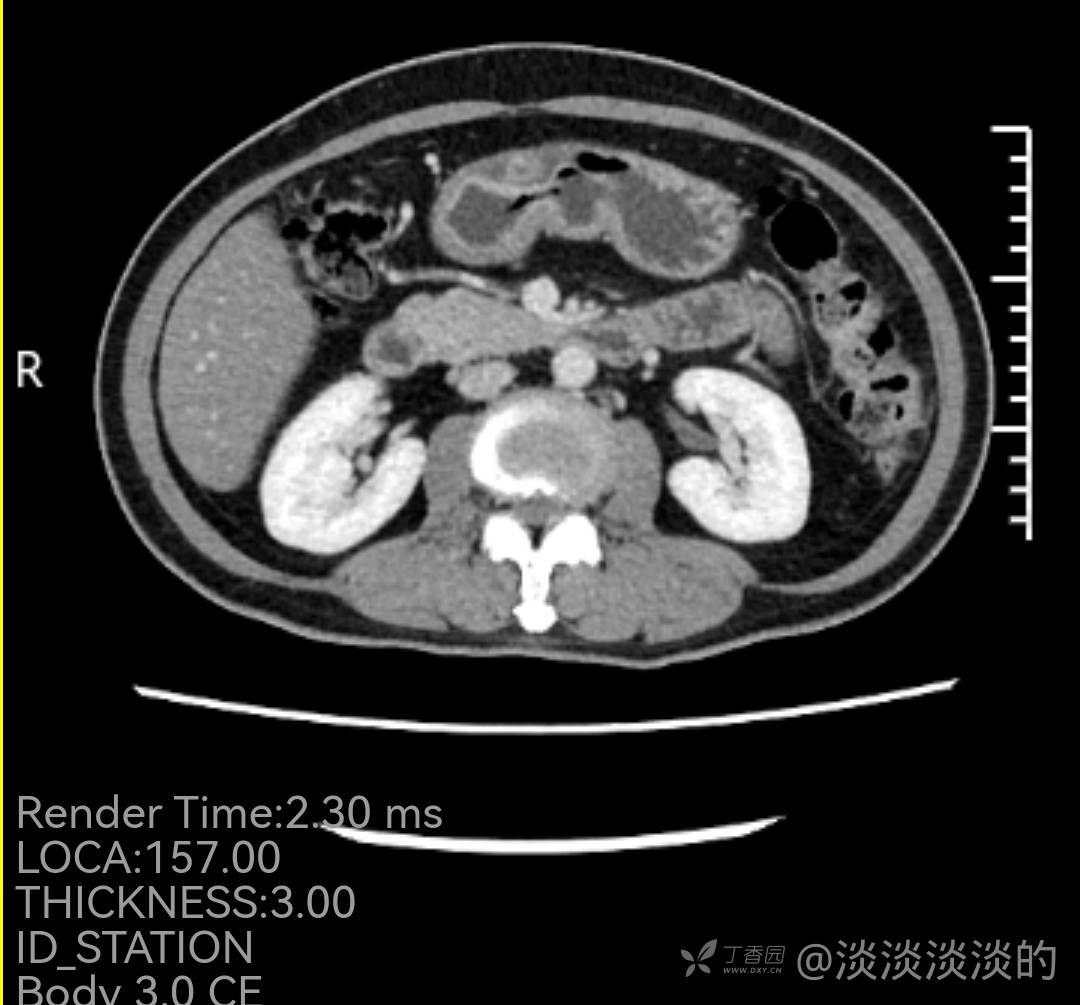

60岁女性,18年胃镜检查提示慢性胃炎,此次因上腹痛1月就诊,门诊检查发现胃窦前壁近胃角一病变,内镜,病理,增强CT如下,常规化验血检查没有明显异常,因病理良性,复查胃镜见最后1张,活检报告未出。